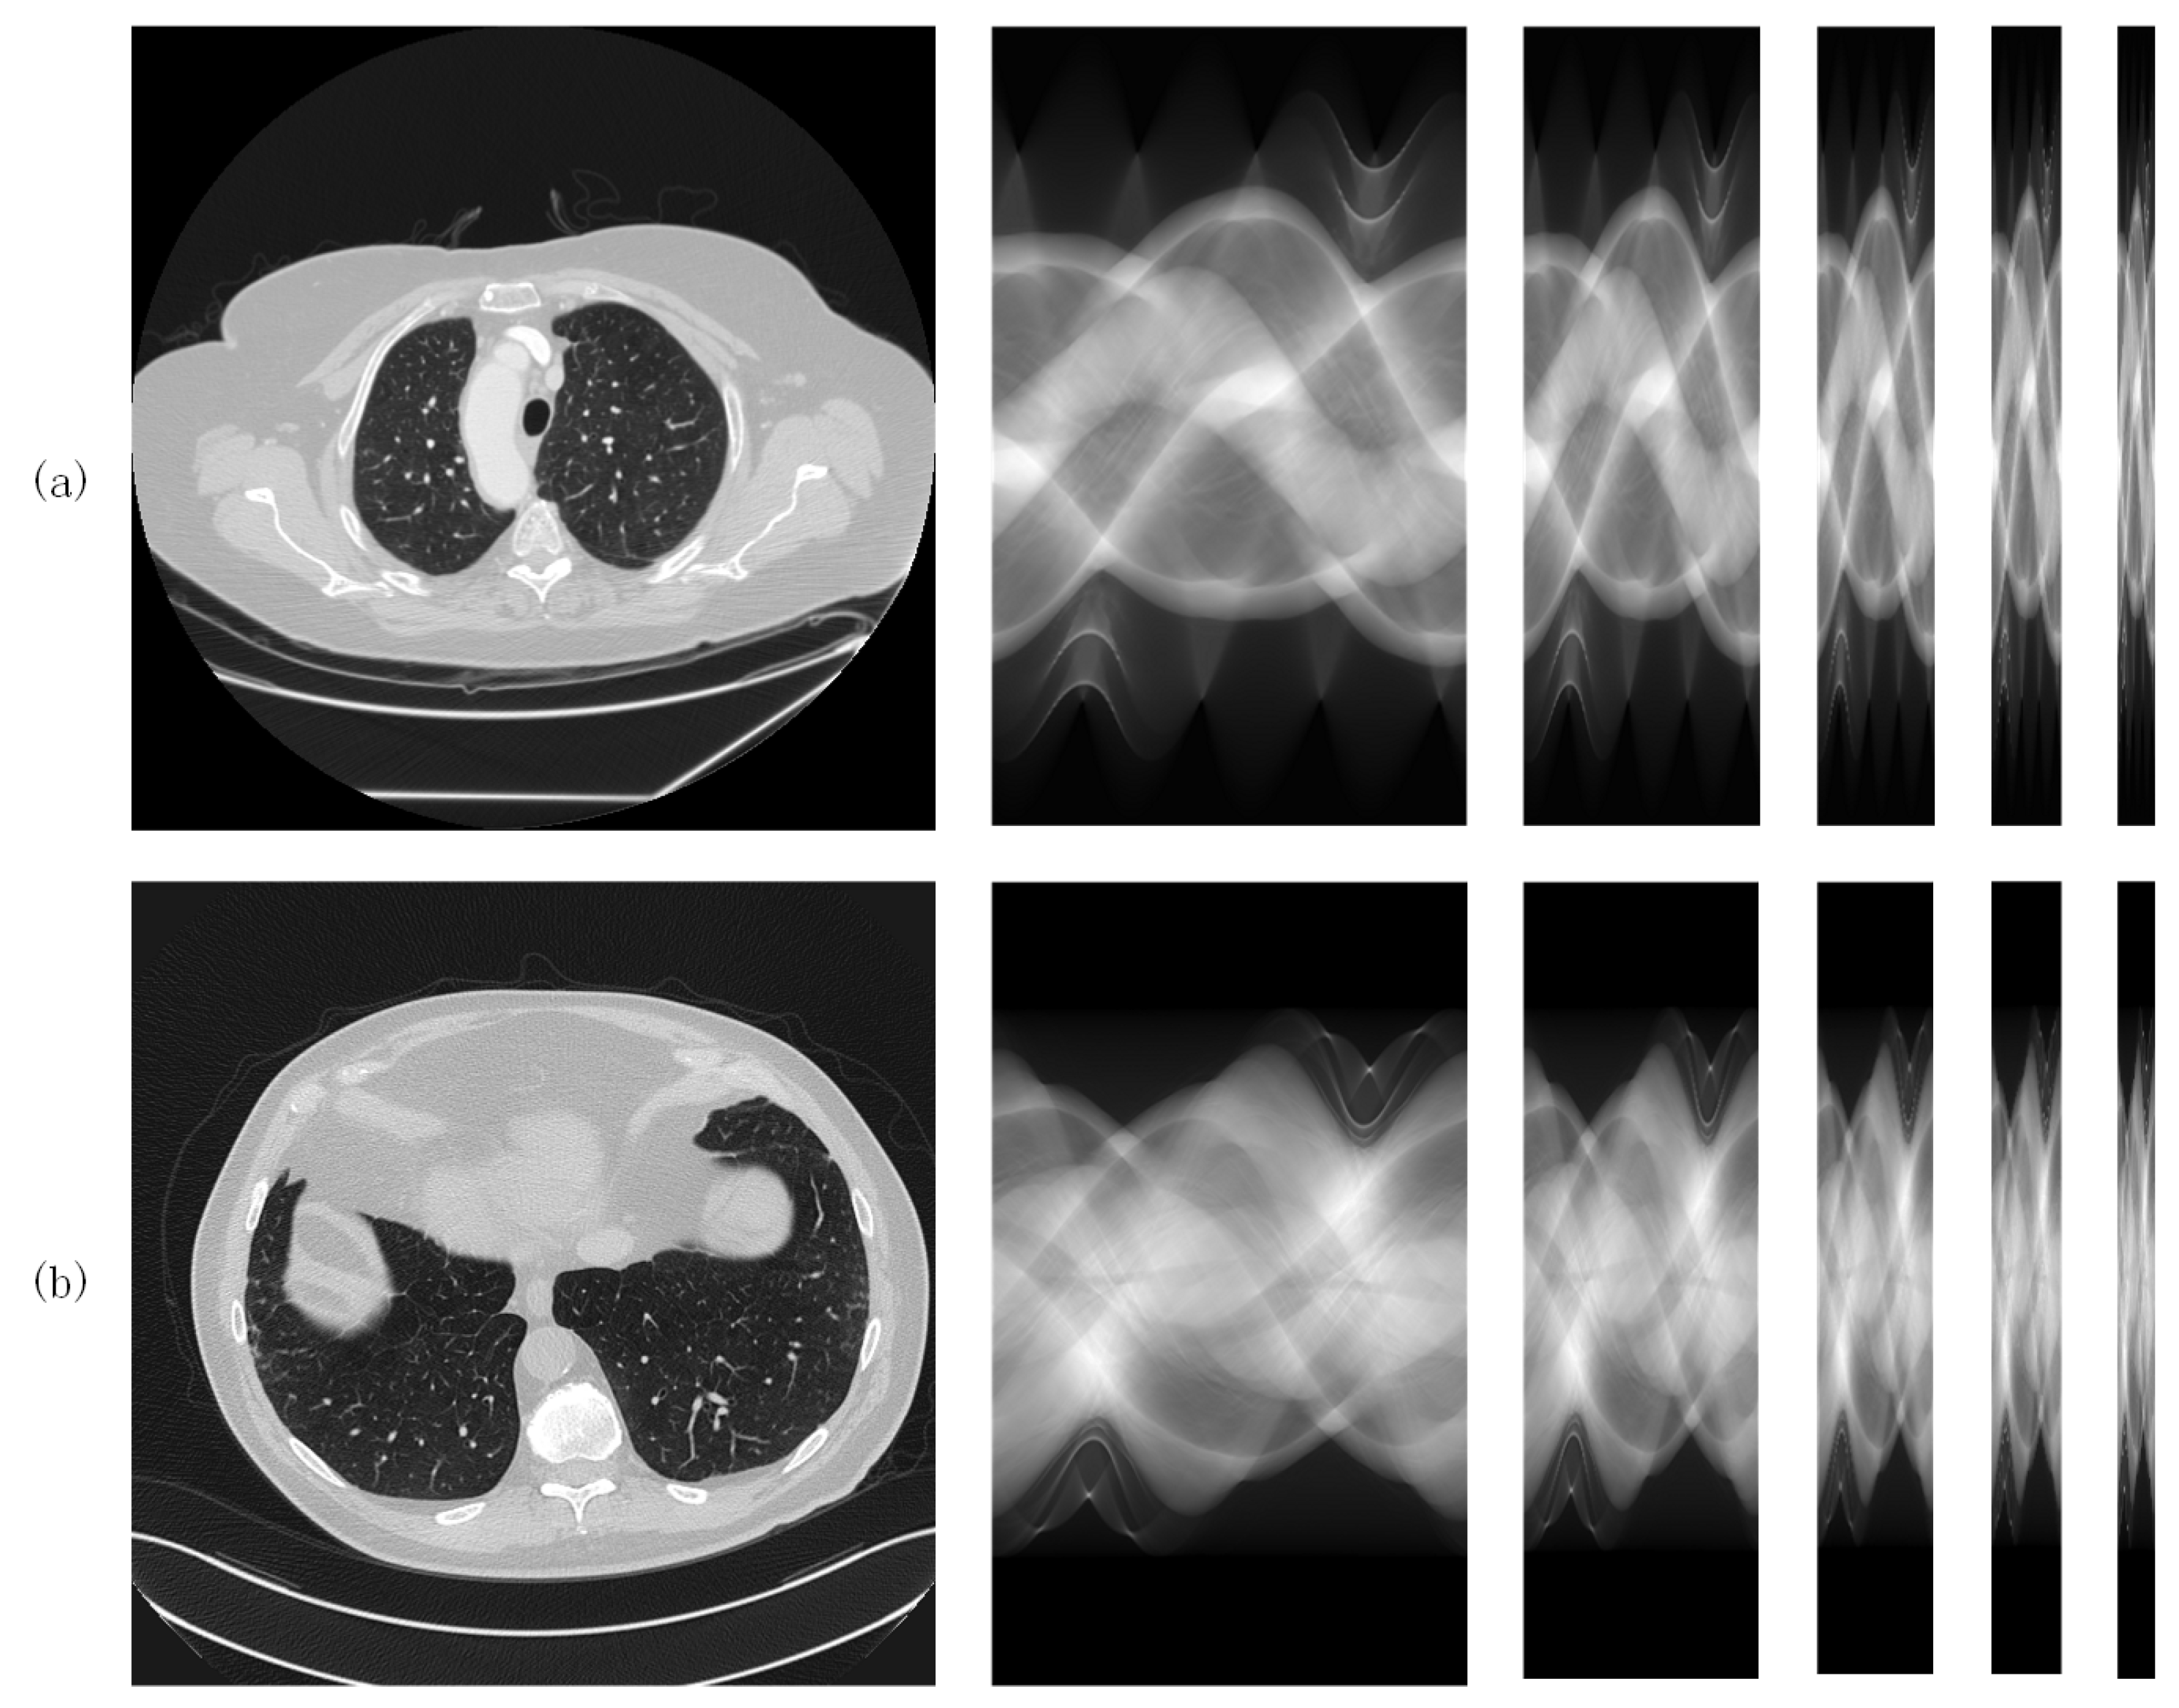

Both datasets consist of 2000 images of the lungs from ten patients (200 images per patient). CT images are squares of size 512. The same data pre-processing method was applied to the two datasets. Full-view sinogram domain data were derived from full-view CT images by the forward projection procedure [31], which can be implemented using the Matlab 2020a function . The size of the full-view sinograms obtained by the fan-beam projection is , i.e., 605 detectors with 360 projection views (sampling interval = 1 degree). The sparse-view sinograms for sparse levels were obtained by downsampling the full-view sinograms in the view dimension with the corresponding sparse levels. For each dataset, 1800 samples were used to train the networks and the remaining 200 samples were used for testing. Figure 3a,b shows the samples from both datasets, which are from left to right, original (normal dose) CT images, full-view sinograms and sparse-view sinograms with various sparse levels ().

Figure 3.

CT samples from (a) the LIDC-IDR dataset and (b) the AAPM dataset.